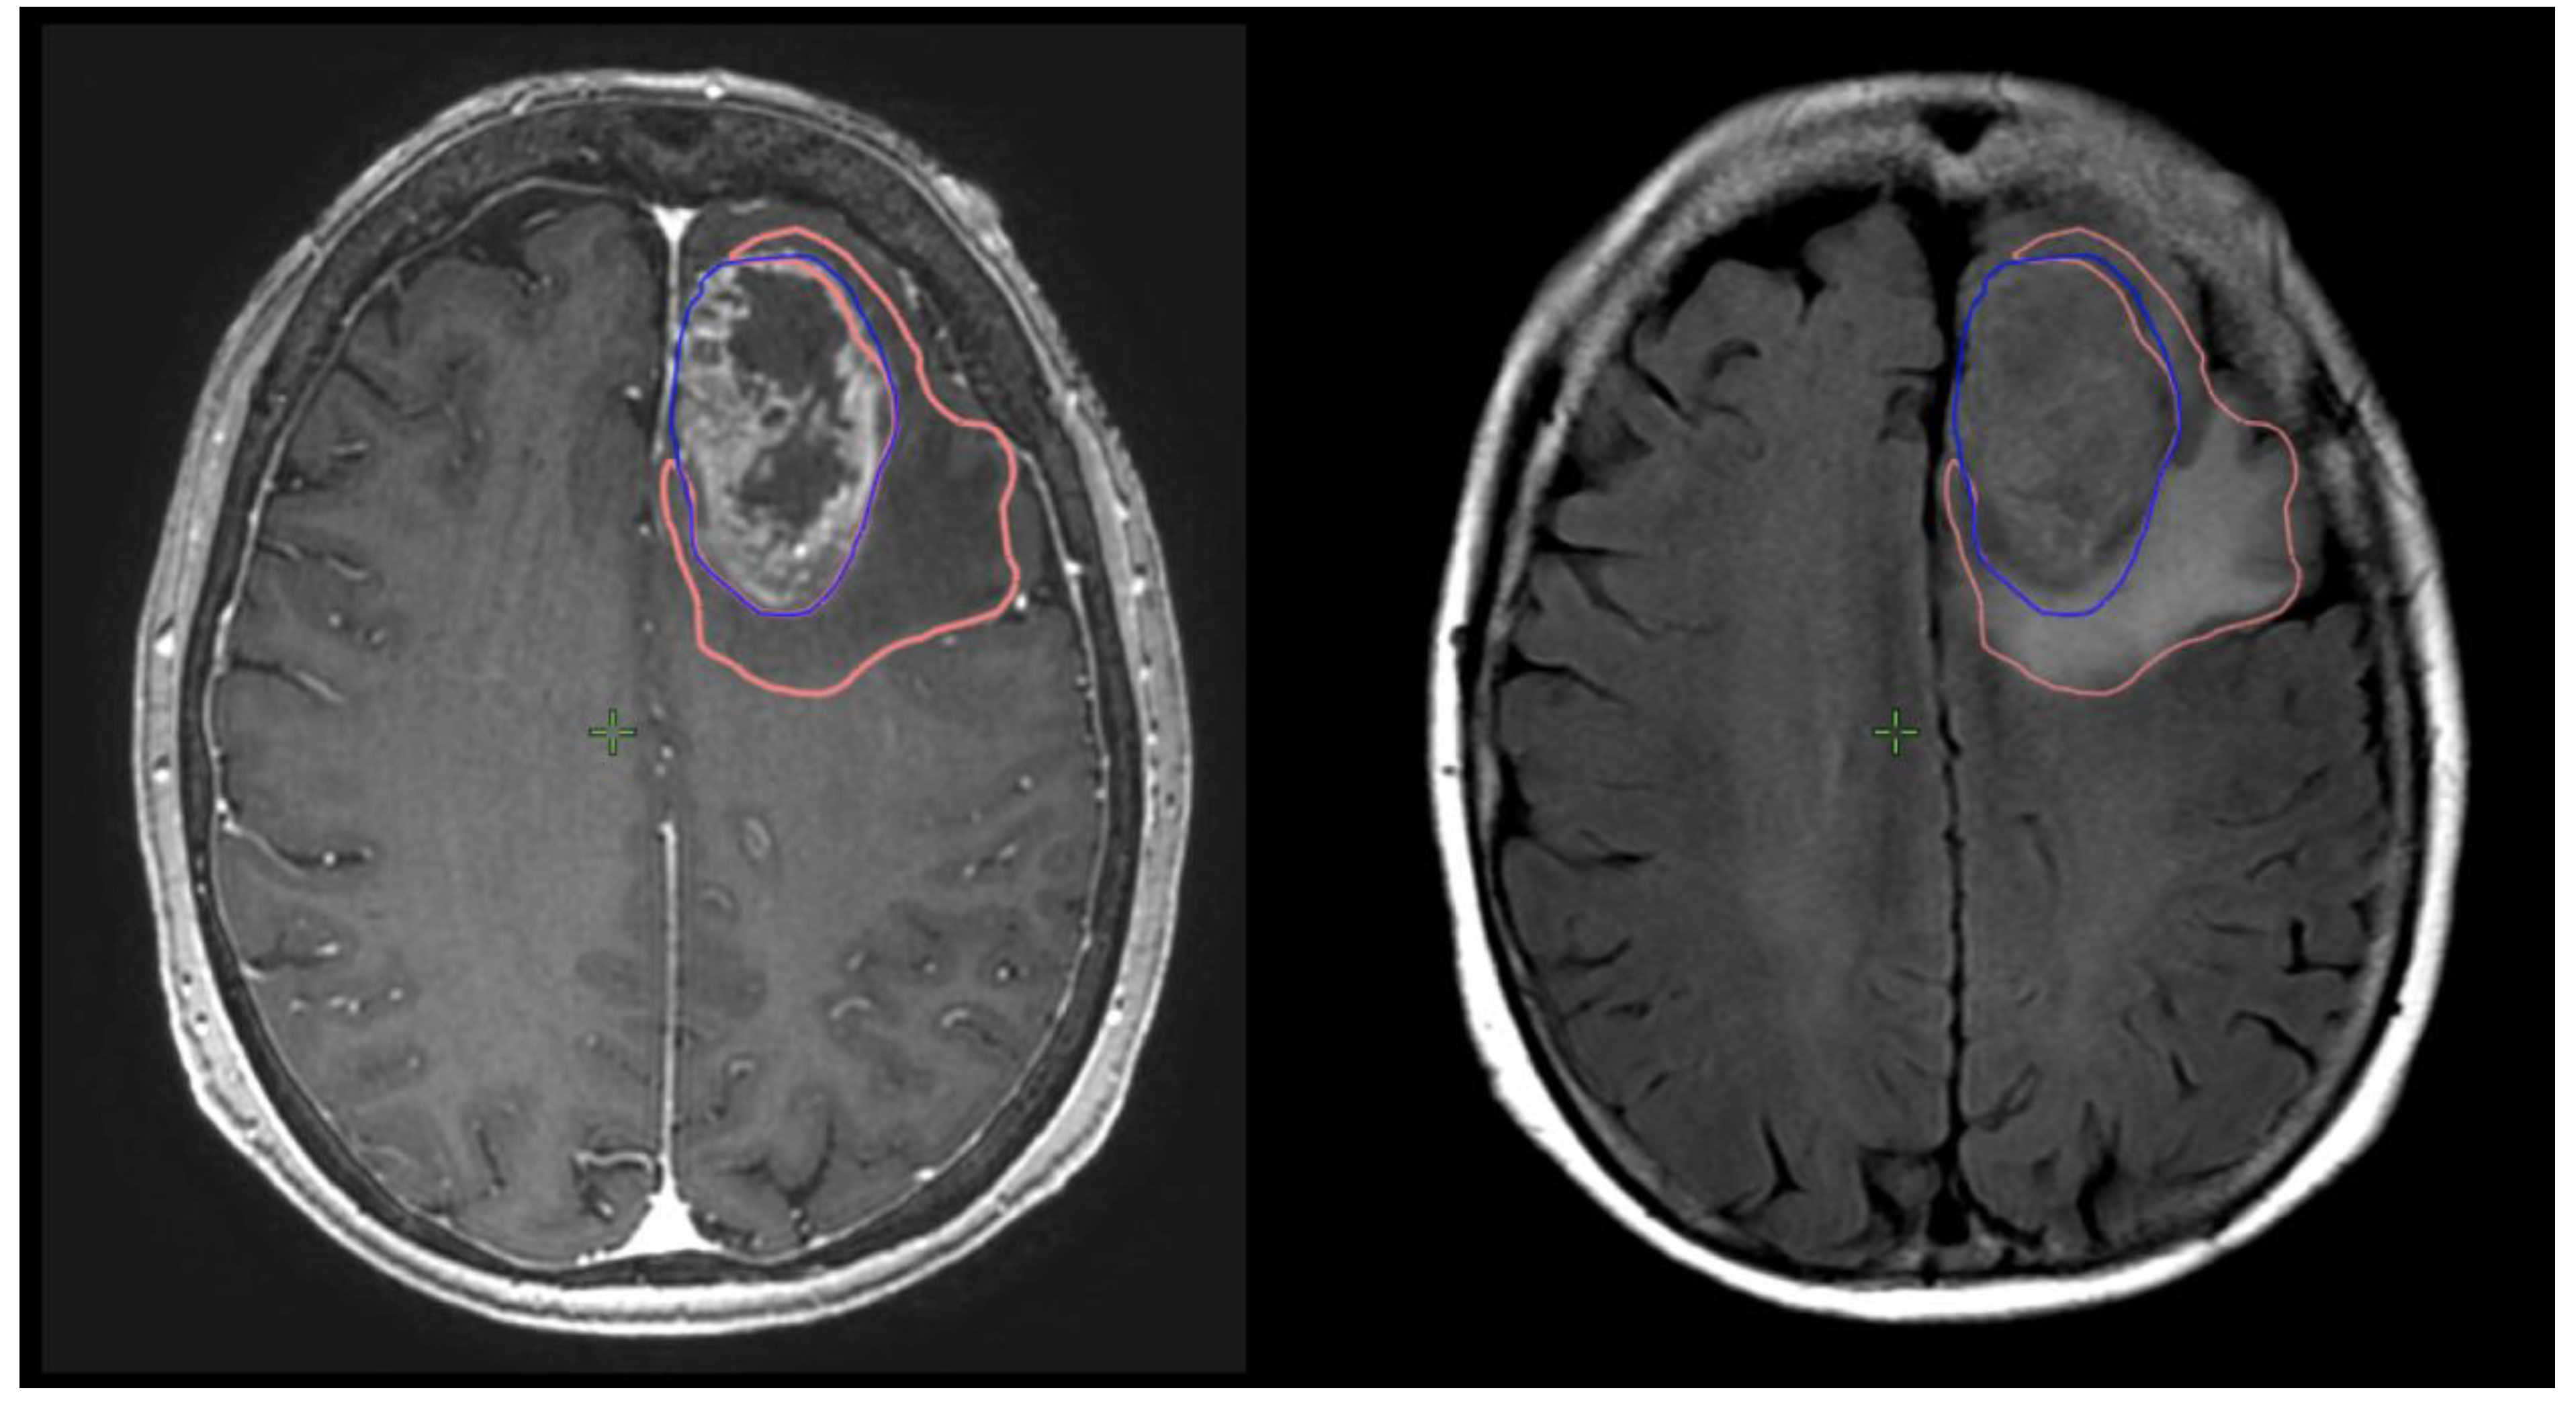

Preoperative and postoperative MRI scans were entered into the radiation planning programme and fused with the registration non-contrast enhanced CT scan. The T1, T2 and T1 gadolinium-enhanced sequences were utilised to manually create volumetric data on both pre- and postoperative scans. The volumes segmented and calculated are demonstrated in Figure 1. These include the preoperative gadolinium-enhancing abnormality (GTVT1gdpre), the preoperative T2 flair abnormality outside of the GTVT1gdpre (GTVT2pre), the postoperative gadolinium-enhancing abnormality subtracted by the blood products on T1 sequence (GTVT1gdpost), and postoperative T2 flair abnormality subtracted by the surgical cavity (T2post). A T2/T1 ratio was calculated from the preoperative volumes (GTVT2pre/GTVT1gdpre), with examples of high and low ratios demonstrated in Figure 2. This T2/T1 ratio was recorded as a continuous variable as well as divided into quartile groups 1–4.

Figure 2. Examples of patients with low T2/T1 ratio on left; and high T2/1 ratio on right. The GTVT1gdpre is shown in blue, and GTVT2pre in orange.